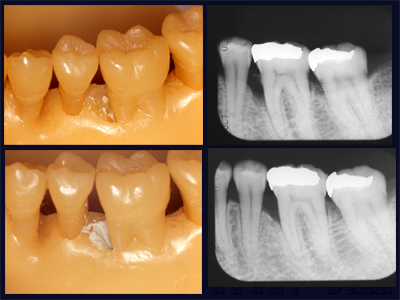

かわかみ実験:レントゲンでの骨頂線の安定のイメージ

さいとう実験:扁心投影でこれほど違ってみえる

これなど「よくもまあここまで、、、」といつもながら見る者を驚かさずにはおられない手の凝りようですが、レントゲンの規格性の重要さもよく理解できます。